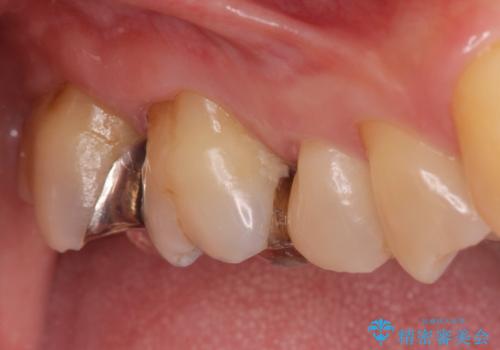

- 冷たいものがしみて飲み物が飲めないとの事で来院。

歯肉が退縮していたので歯周外科手術(歯茎の移植手術)か被せ物で覆う(歯肉退縮しているところまで覆う)の提案をしたところ被せ物がいいとのことでしたので

被せ物の治療のご案内になりました。

適合の良い被せ物が入りました。